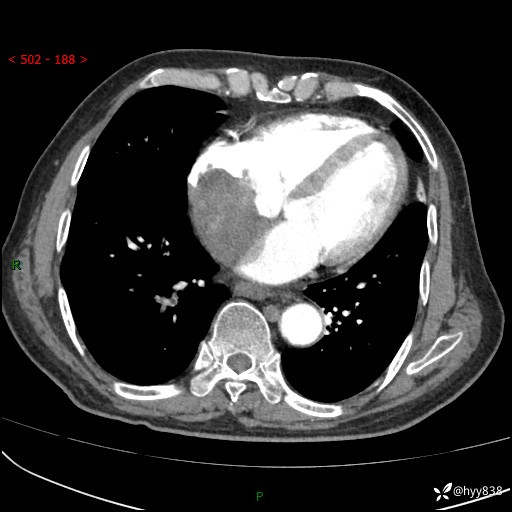

主诉:检查发现心脏肿物1周余。

现病史:患者一周余前因腹胀就诊我院消化科门诊,查心脏彩超提示右房内异常回声(粘液瘤?),无明显心慌、气喘、胸闷,无明显胸痛、咳嗽咳痰等不适,活动量增加后出现心慌、气喘不适。现为求进一步治疗,就诊我科,门诊遂以“心脏肿物”收入院。 自发病以来,精神睡眠一般,食欲尚可,大小便正常,体力下降,体重无明显变化。

胸部CT平扫+增强